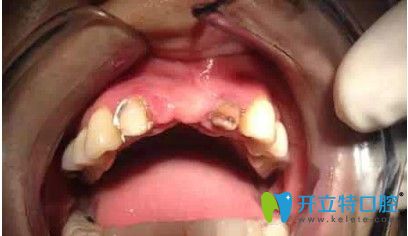

劉女士,33歲,據(jù)她描述,自己多年前在國內(nèi)一家口腔醫(yī)院做了烤瓷冠,但由于時(shí)間長變的松動(dòng),考慮到自己還年輕,為了一步到位,她來韓國安特麗做了多顆牙種植。

在拆除烤瓷橋后,發(fā)現(xiàn)她的口內(nèi)埋伏牙,把埋伏牙拔除后,很順利的植入了種植體,完成了種植牙。